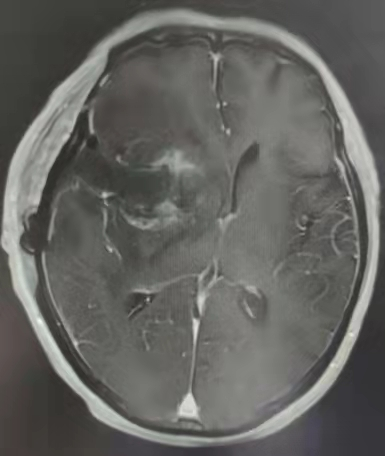

近日,自贡市第四人民医院神经外科收到一面材质和做工都相当精美的锦旗。咋子回事安?原来,72岁的黄爷爷头昏、头部持续性胀痛、左侧肢体乏力已经两个多月了,在外院行核磁共振(MRI)提示:右侧基底节区占位性病变。于外院对症处理后症状未缓解,遂来到自贡四院神经外科需求治疗,诊断为右岛叶胶质瘤。

术前MRI提示右侧岛叶占位性病变